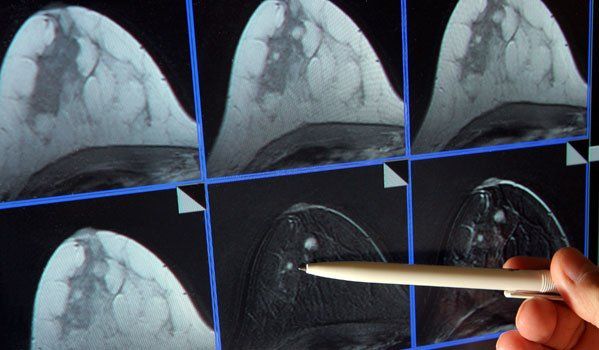

Die Mammografie ist eine Röntgenuntersuchung. Dabei wird eine Brust nach der anderen zwischen zwei Kunststoffplatten zusammengedrückt. Viele Frauen beschreiben die Untersuchung als unangenehm, manche als schmerzhaft, andere wiederum empfinden sie als unproblematisch. Die Untersuchung dauert einige Minuten.

Ultraschall alleine eignet sich im Normalfall nicht zur verlässlichen Früherkennung von Brustkrebs. Sollte das Brustgewebe sehr dicht sein oder bei der Mammografie etwas Auffälliges entdeckt werden, wird die Radiologin/der Radiologe zusätzlich zur Mammografie eine Ultraschall-Untersuchung (Sonografie) durchführen.

Bei einem auffälligen Befund wird die Situation durch weiterführende Untersuchungen (z.B. Magnetresonanz, Biopsie) abgeklärt.